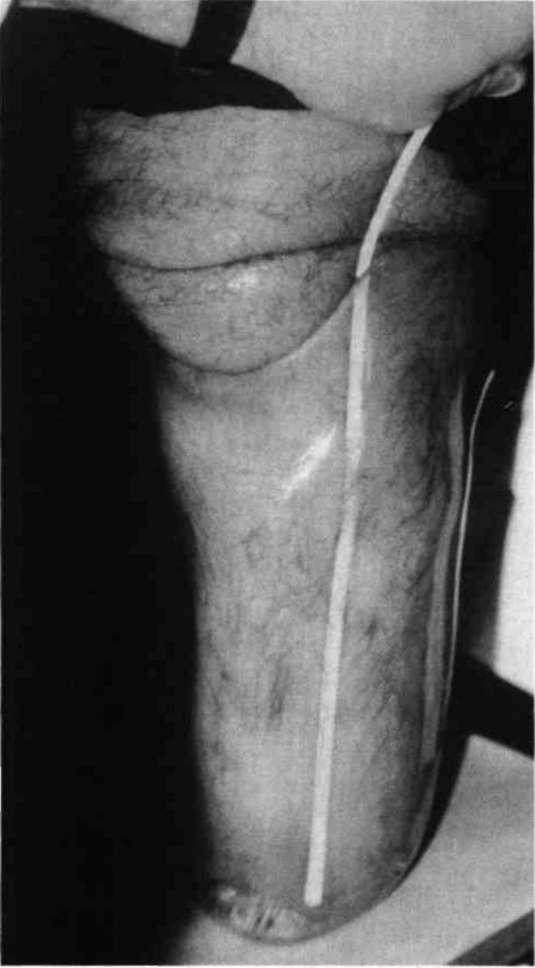

The socket is sanded lightly on the inside to promote adherence of the alginate, and escape holes are drilled medially and laterally approximately one inch proximal to the distal end. Small pin holes are also drilled over void areas to allow air to escape as the alginate fills. The water and powder are mixed with an electric drill and paint stirrer, and then poured into the test socket and slushed around the walls to completely coat the inside of the socket. The patient then enters the socket and stands with equal weight-bearing bilaterally. The alginate fills void areas, establishing total contact. The excess is evacuated, and gelling occurs in one to three minutes (Fig. 4 and Fig. 5). The patient is then seated and the socket is carefully removed, after breaking the suction seal. The alginate will adhere to the inside of the socket.

Figure 4. Alginate fills void areas while patient bears one half of his weight into the socket. Excess alginate flows through small relief holes drilled for this purpose.Figure 5. Alginate solution cures between one and three minutes.